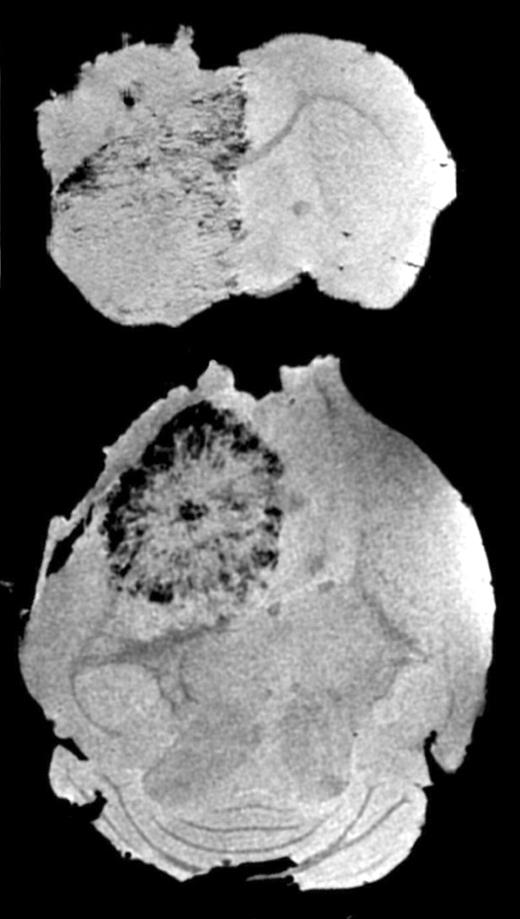

Serial MRI in mice that received magnetically labeled Sca1+ bone marrow cells, group 2. See the complete figure in the article beginning on page 420.

In this issue of Blood, Anderson and colleagues have used magnetic resonance imaging (MRI) to follow magnetically labeled transplanted cells. In the reported studies, Sca1+ endothelial progenitor cells were labeled with superparamagnetic iron oxide nanoparticles (SPIOs) and then injected into the vasculature of animals. In mice with orthotopically implanted gliomas, the labeled cells tracked to the tumor periphery and were initially visible by MRI as a slight darkening surrounding the tumor 9 days after implantation. At later time points, the darkening became more pronounced and progressed to a significant hypointense ring surrounding the tumor. Ex vivo high-resolution MRI (see figure) showed that labeled cells were also infiltrating into the interior of the tumors. In temporal studies, histology demonstrated that MR signals were present only when tumors were undergoing neovascular growth, and immunohisotchemistry confirmed that iron-containing cells within the tumor and its periphery were positive for 2 endothelial cell markers, CD-31 and von Willebrand factor. Although the study did not control for the potential leakage of iron from the transplanted cells and subsequent redistribution to vasculature, there are significant data from other studies to strongly suggest that this is not the mechanism in place.3  Furthermore, the use of labeled nonviable cells for control animals supports the authors' conclusions that ex vivo–labeled progenitor cells migrate and differentiate into endothelial cells and are responsible for the signal changes observed.